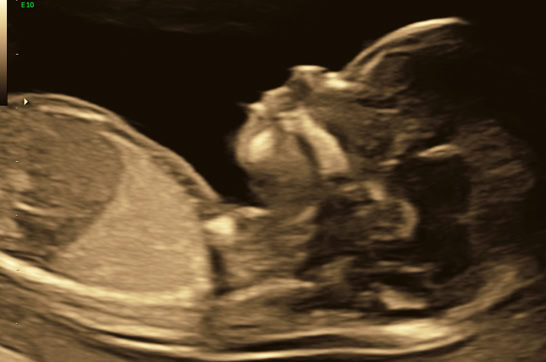

Embryo in der 12. SSW im 3-D Ultraschall

Embryo 12. SSW